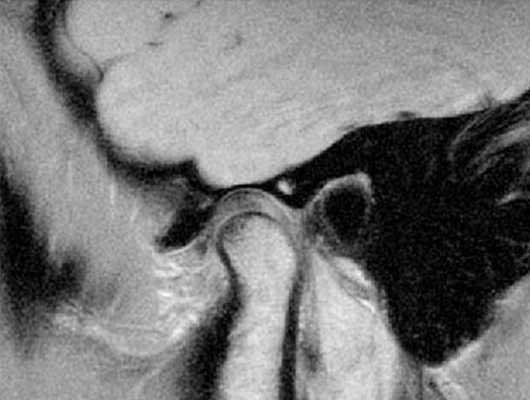

МРТ зубов что показывает

Магнитно-резонансную томографию рекомендуют использовать для определения состояния рыхлых структур, клетки которых содержат большое количество воды. МРТ зубов практически не назначают по причине низкой информативности исследования в отношении твердых тканей (дентина, эмали).

Снимок МРТ правого височно-челюстного сустава

Метод основан на явлении магнитного резонанса. В ответ на направленное действие индукционного поля атомы водорода в диполях воды меняют положение. Чувствительные детекторы считывают отклик и передают информацию на компьютер для дальнейшей обработки. С помощью программного обеспечения полученные данные преобразуют в серию послойных изображений сканируемой зоны.

Делают ли МРТ зубов?

Магнитно-резонансную томографию челюстно-лицевой области назначают при наличии у пациента противопоказаний к рентгенографии и КТ. Методы, основанные на применении ионизирующего излучения, обладают большей информативностью в отношении зубов и костей.

Снимок МРТ височно-нижнечелюстного сустава

Какие заболевания челюсти выявляет МРТ?

Магнитно-резонансная томография позволяет диагностировать воспалительные, дегенеративные, дистрофические процессы. Метод применяют для определения характера кровоснабжения нижней, верхней челюсти и ВНЧС, уточнения локализации новообразований.